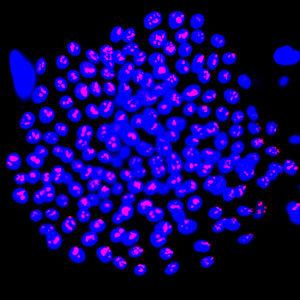

ATP-binding-cassette G2 (ABCG2)-positive skin cells (blue) show positive staining of cell proliferation marker Ki-67 (red), which marks cells with the most growth potential.

© 2016 Dongrui Ma, Singapore General Hospital

“Cultured grafts are usually very fragile,” says Birgit Lane from the A*STAR Institute of Medical Biology. Researchers sought to ‘enrich’ and fortify the grafts by including more stem cells, a cell type with potent tissue repair capability. They needed a cellular marker to identify skin stem cells: a protein usually tasked with evicting foreign chemicals from cells, ATP-binding-cassette G2 (ABCG2), fitted the bill.

Promisingly, “ABCG2 is a cell-surface marker, so we can isolate live cells using a cell-sorting technology,” says Dongrui Ma, the paper’s lead author. Often, stem cell markers cannot target live cells, which limits their clinical applications.